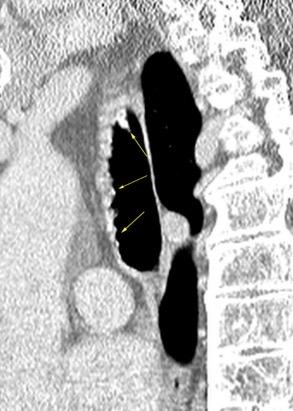

Traqueobroncomegalia de Mounier-Kuhn

Dilatación marcada de tráquea y grandes bronquios.

Traqueobroncomalacia 67% + Protrusión del tejido músculo-membranoso redundante entre los anillos cartilaginosos.(diverticulosis traqueal)

Infección respiratoria recurrente (88%)

Debilidad del aparato muco -ciliar Fumadores.

Schmitt P et al. Respiratory Conditions Associated with Tracheobronchomegaly (Mounier-Kuhn Syndrome): A Study of Seventeen Cases. Respiration 2016

Wegner F. CT of Mounier-Kuhn Disease. Radiology 2020